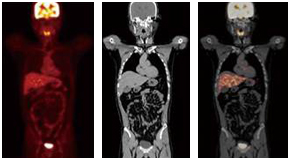

- 간암: 간 내 종양의 형성은 CT에서 명확하게 확인될 수 있으며, 조기 발견이 치료에 중요한 영향을 미칩니다.